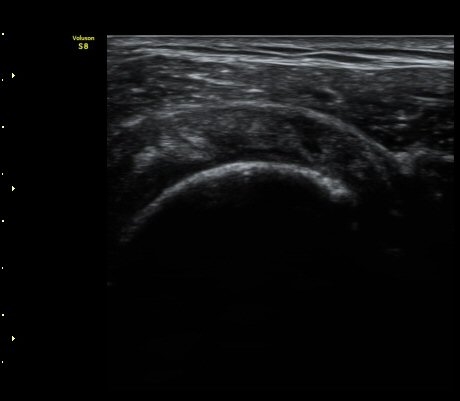

ÃÊÀ½ÆÄ °Ë»ç

2049205267_ba00cba1_IMG_20140331_2_3-c.jpg